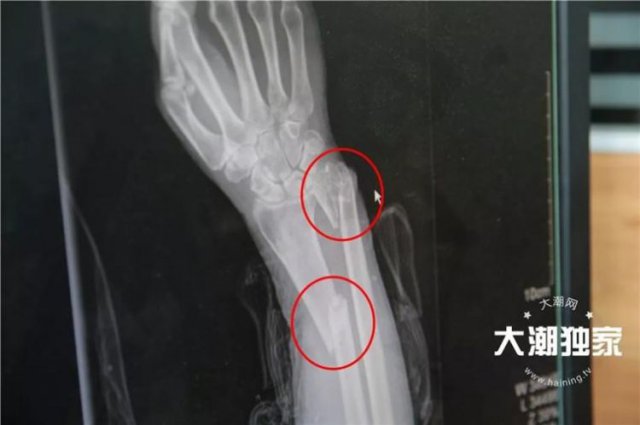

突发车祸,68岁老太被压车底 之后的一幕太震撼

浙江海宁市区育才路九虎路口 发生一起交通事故 当时一名行人由东往西过马路 这个时候 一辆银色轿车由东往南左转 突然撞到了由东往西过马路的行人 撞到行人后 可能驾驶员也慌了 没有刹车 反而直...